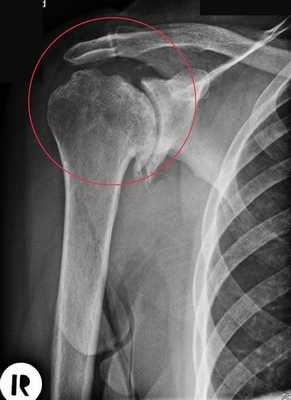

Артроз плечевого сустава на рентгене.